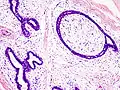

| Histopathologic image of breast fibroadenoma. Core needle biopsy. H&E stain. | |

Histopathologic image of breast fibroadenoma. Core needle biopsy. Hematoxylin & eosin stain.